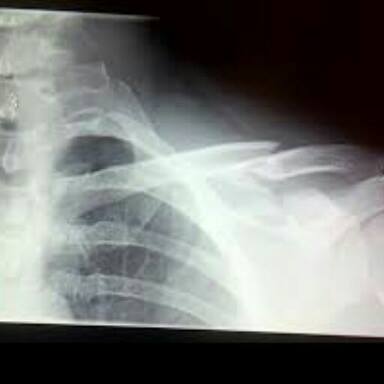

UDINE – Joe Bastianich cade e si rompe una clavicola. Il ristoratore e star di Masterchef Italia è caduto in montagna sul monte Zoncolan, in Carnia, dove è in vacanza, e si è fratturato la clavicola e due costole.

A dare la notizia dell’ infortunio è stato lo stesso Bastianich, che su Facebook ha pubblicato la radiografia della clavicola, aggiungendo: “Epic crash”, e ringraziando i medici dell’ospedale di Udine che lo hanno curato.